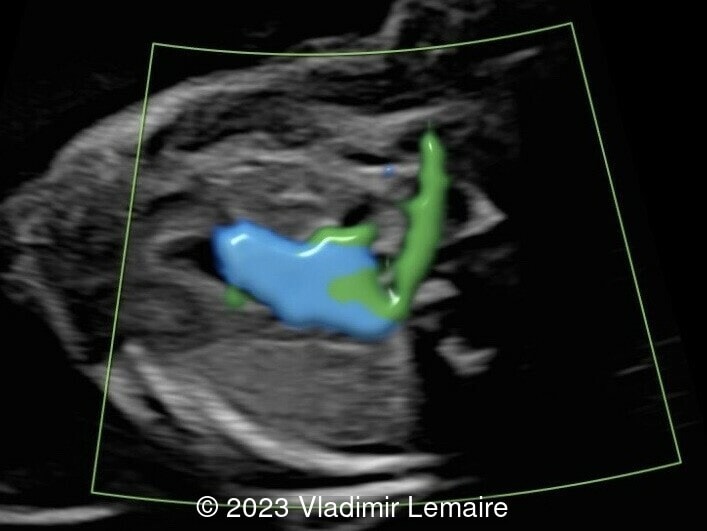

Aberrant right subclavian artery, seen in green, in the same fetus.

Image 4 Aberrant right subclavian artery, seen in green, in the same fetus.